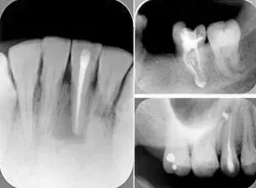

6. 術(shù)后 X 線片

術(shù)后 X 線片用來評定根管充填 長度、致密度(管壁清晰、側(cè)枝)等指標(biāo)。

圖為根管充填術(shù)后 X 線片。圖中可見,根管充填較好。右下圖有白色小點,為側(cè)方加壓導(dǎo)致糊劑擠出所致,表明根管充填比較致密。

致密、恰到好處的充填可去除干凈根管里感染灶,機(jī)體逐漸恢復(fù)。

多根牙時候需進(jìn)行偏移投照,正位投照無法說明具體哪根牙根管充填效果。